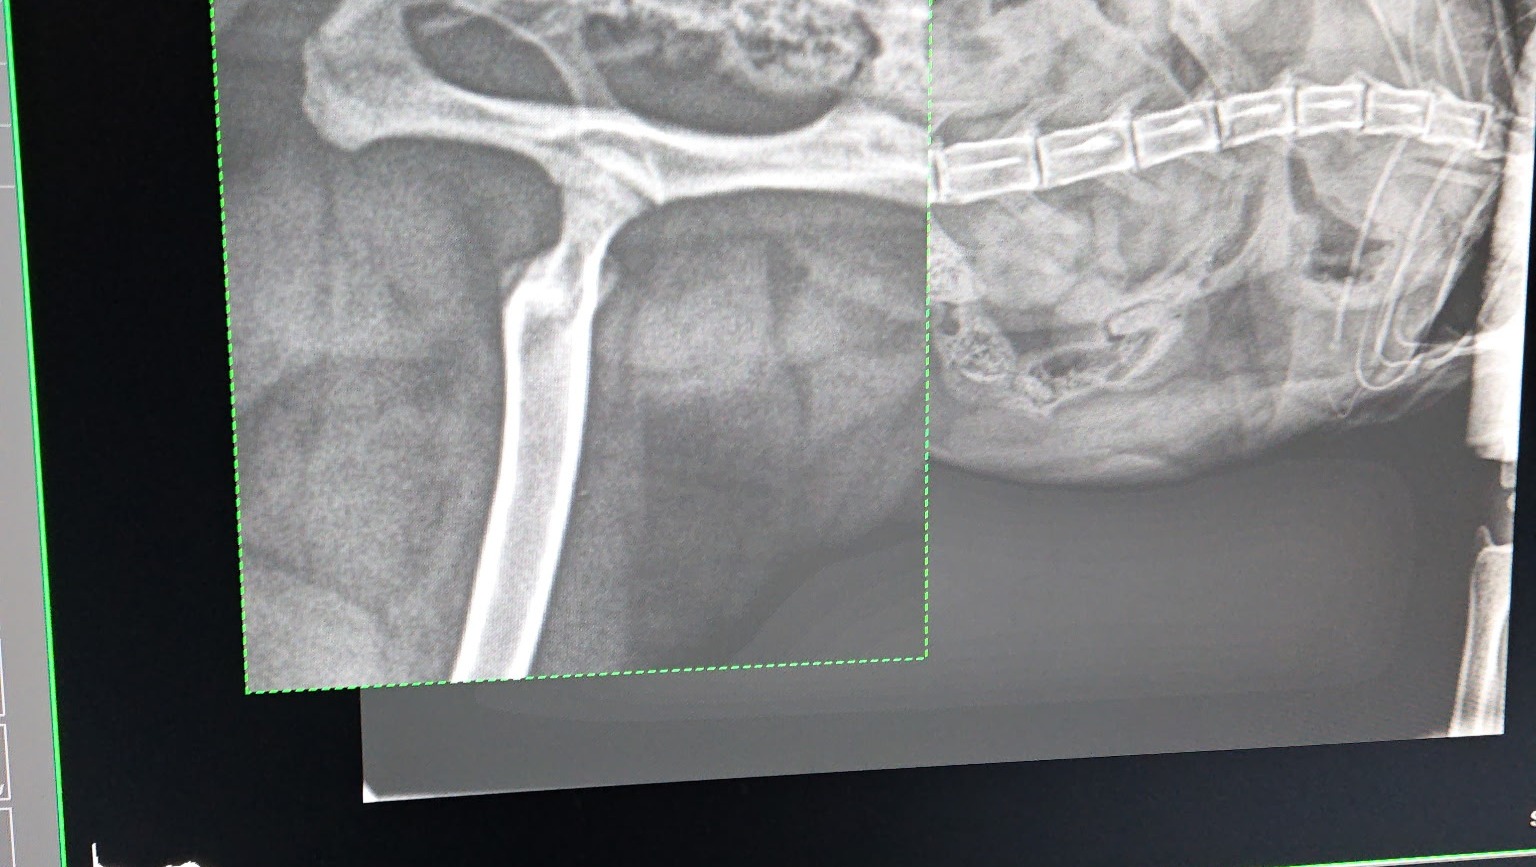

Hi. This is a first for me, but i am in a bad situation with my Ragdoll, Blaze. Blaze is not even 2 years old and he needs extensive and expensive surgery to repair his hip. The surgery needs to be done by an orthopedic surgeon. Unfortunately I did not purchase pet insurance when I bought him and now that it is a pre existing condition, all the pet insurances I looked at won't cover his surgery. Any help would be greatly appreciated. Blaze if he could tell you would appreciate it too.